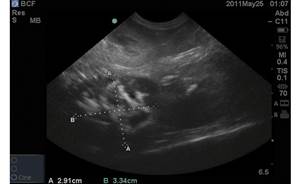

Обычно диагноз «пиометра у собаки» появляется в карте животного, когда на УЗИ находят расширенные, заполненные жидкостью рога матки. Поводом для обращения владельца к врачу могут быть выделения из петли: красноватые, желтоватые или слизистые, вялость животного, отказ от корма, повышенная жажда и, соответственно, увеличение объема мочи, однако расширение рогов матки может быть и случайной находкой.

Итак, при высоком уровне гестагенов (или высокой чувствительности к гестагенам) внутриматочные железы разрастаются до видимых на УЗИ пузырьков, иногда до

Таким образом мы имеем кистозную (кисты – это пузырьки) гиперплазию (утолщение) эндометрия: гормонозависимое заболевание. Как видите, про гной пока никакой речи не идет и при «стерильной» кистозной гиперплазии эндометрия системных симптомов (жажда, вялость, рвота, отказ от еды) может не появляться.